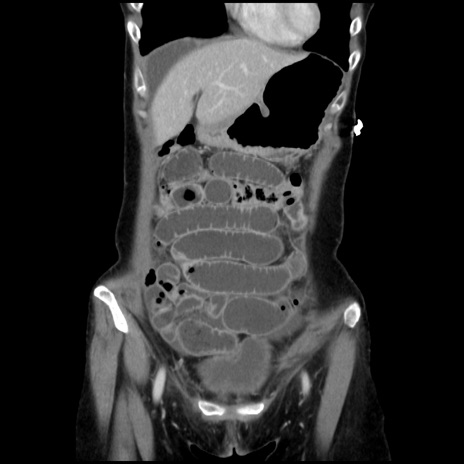

症例32(冠状断像)

【症例】40歳代 女性

【主訴】上腹部痛、嘔気・嘔吐

【現病歴】約9時間前頃から急に上腹部痛、嘔気、嘔吐が出現。改善しないため救急要請。

【既往歴】子宮頚癌(広汎子宮全摘術、放射線療法)、腸閉塞

【身体所見】腹部:平坦、軟、腸雑音亢進、上腹部を中心に腹部全体に圧痛あり。

【データ】WBC 8400、CRP 0.03